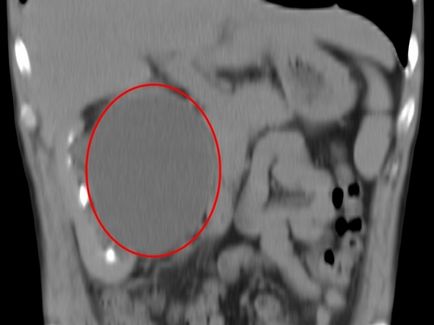

Parapelvikalnaya tumor

Parapelvikalnaya vese ciszta, egy fotó amely publikációkat a fenti hatással lehet nemcsak a bevonat réteg, hanem behatolnak a vesék, a test, ami miatt a beteg lehet diagnosztizálni többszörös szervi elégtelenség.

Daganatok a nagyméretű

Úgy néz ki, mint egy ciszta ultrahangra fenti képen látható összes részletet. Általában ciszták a képek jelennek meg egy közepes vagy nagy méretű foltok vagy eszméletvesztést néhány ág vagy csatornákat.